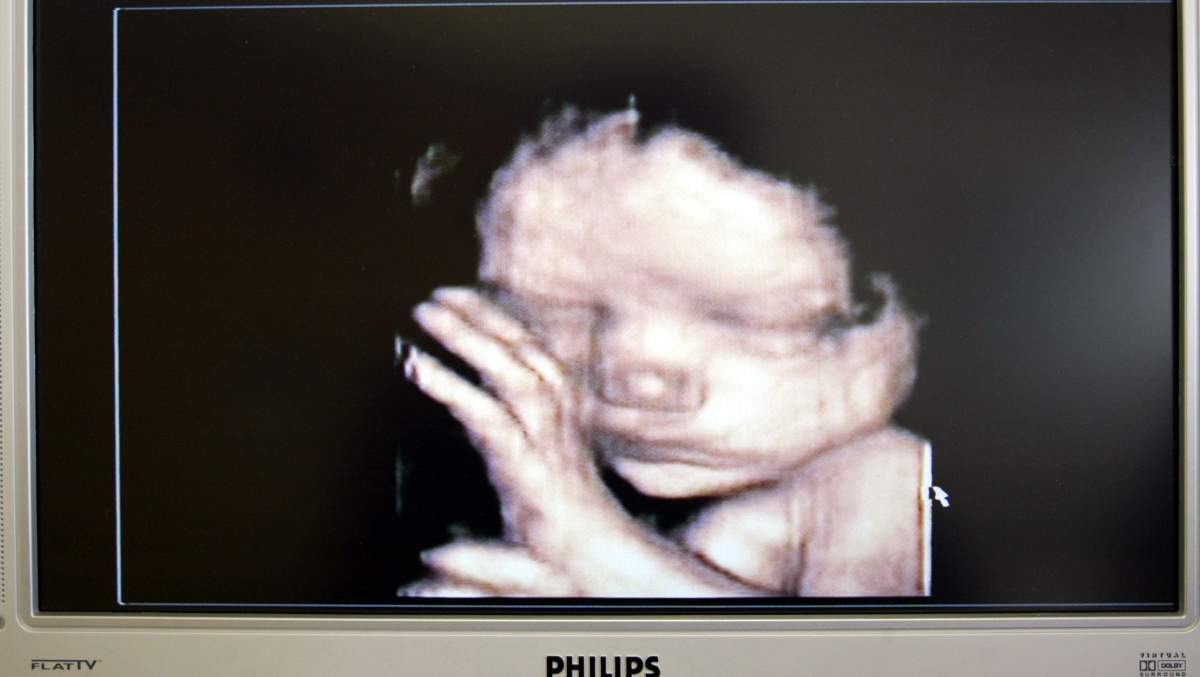

“Definitivamente me sorprendió que nos quedamos embarazadas tan rápido con este bebé!” Catelynn dijo a Celebuzz en una entrevista exclusiva el 22 de febrero. “Pero estamos tan emocionados”. Tyler, de 28 años, estaba sorprendido por las noticias. Al principio, no lo creía, dijo el nativo de Michigan. Acabo de darle la prueba positiva. Tyler se mantuvo dudoso sobre el embarazo de su esposa hasta que se perdió su período y luego tomó otra prueba, que volvió positiva. Las cámaras de MTV estaban allí cuando Catelynn y Tyler se enteraron de que estaban esperando otro bebé, pero la pareja incluso escondió las noticias de los productores inicialmente. “[Nosotros] esperábamos hasta que yo estaba más adelante para mencionarlo en el espectáculo!” explicó.

La estrella anunció las noticias sobre las redes sociales compartiendo una foto de la hija de 6 años Nova y la hija de 2 años Vaeda con una señal que decía que serían hermanas grandes en 27 semanas. Catelynn y Tyler también son los padres de Carly Davis, a quien colocaron para su adopción cuando nació. Tyler compartió un post similar. “No puedo esperar otra hermosa bendición”, escribió en Instagram. “El arco iris valía la pena. El bebé Baltierra vendrá pronto. Fellow Adolescente mamá papá Cory Wharton llegó a Tyler para celebrar las buenas noticias. Felicitaciones por el Sí, escribió.